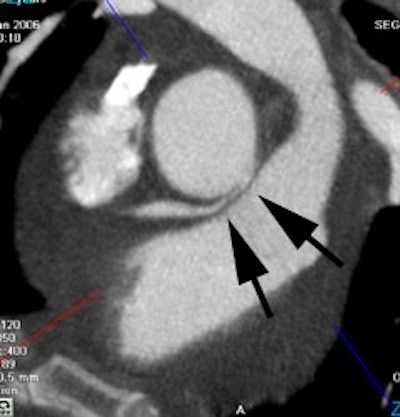

Anomalous RCA origin

from the left coronary sinus: The patient below underwent

coronary CT angiography to assess for coronary artery

disease. The patient was found to have an anomalous

RCA arising from the left sinus of valsalva. The

vessel can be seen to course between the pulmonary

trunk and aorta (black arrows) |